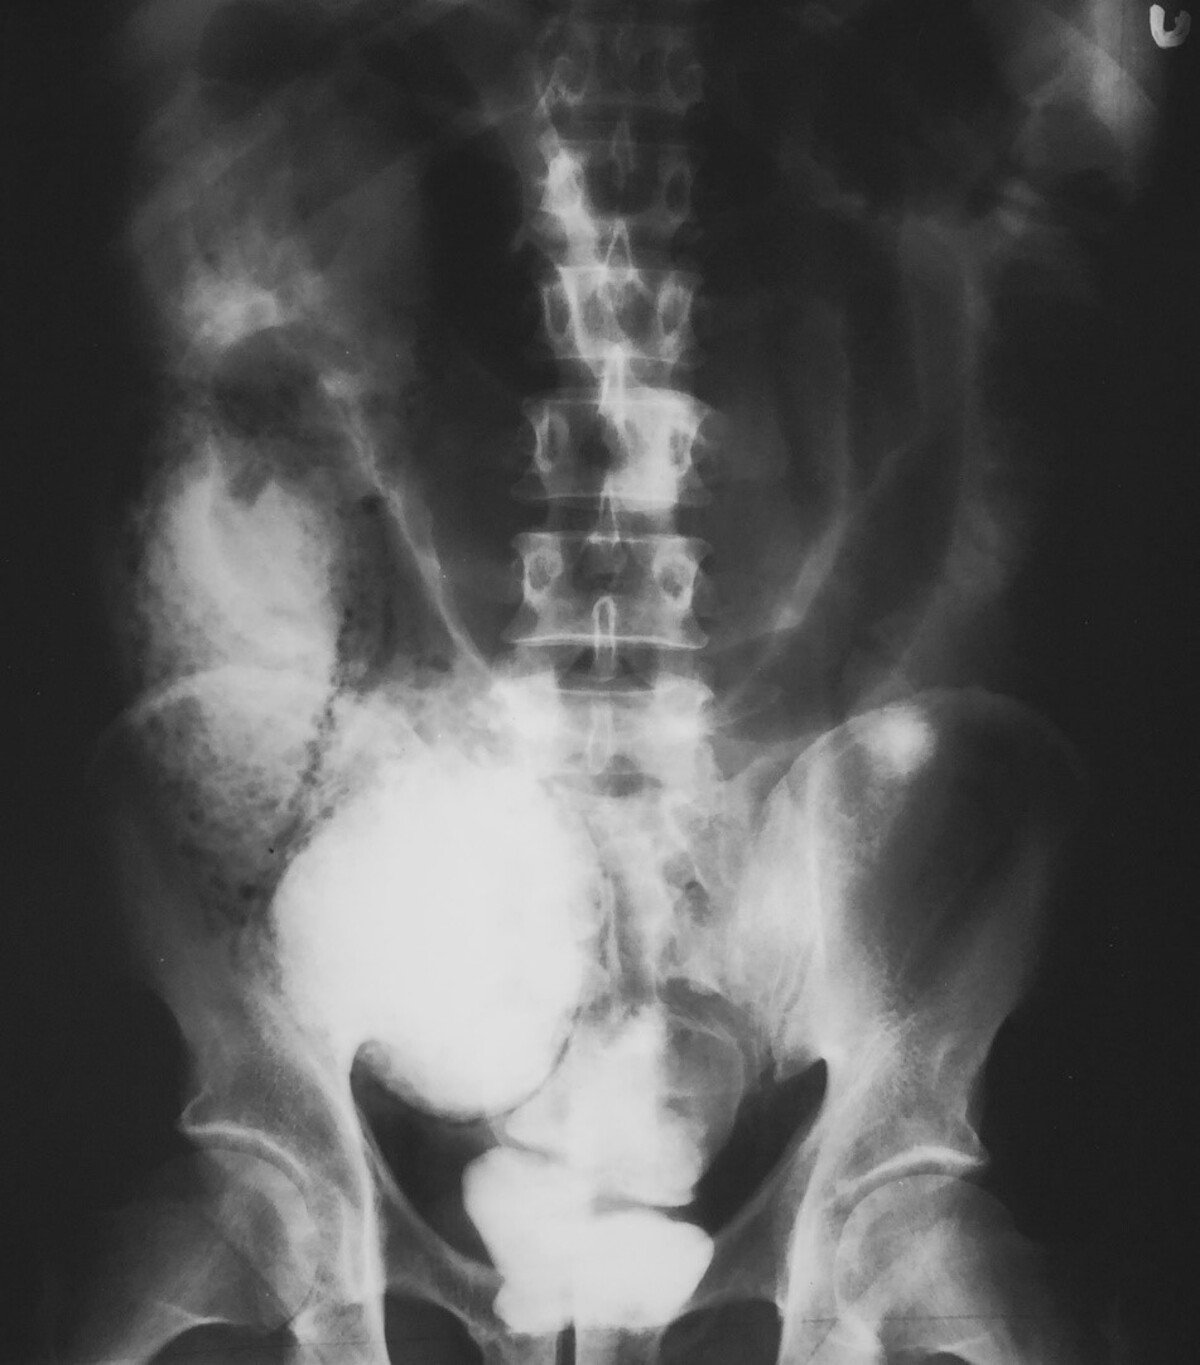

A 62-year-old man with a history of hypertension, coronary artery disease following stent placement 2 years ago, and chronic obstructive pulmonary disease presents to the emergency department with acute onset of abdominal pain. He takes clopidogrel and lisinopril. His pain is described as a 9/10 on the right side and a sharp band throughout his abdomen. He has watery diarrhea that started when the pain began. He has had 3 bowel movements since the onset of his symptoms and undergoes an initial x-ray [figure]. What is the best next step in the management of this patient?

The x-ray shows pneumatosis linearis lining the right colon. In this circumstance, there is a concern for isolated right colon ischemia and possibly concomitant acute mesenteric ischemia. The most critical next test is an angiographic study to delineate how best to treat the patient. CT of the abdomen and pelvis alone might miss a vascular obstruction that requires immediate interventional radiology or vascular surgical intervention. Calling surgery for an emergency laparotomy might be best if there was clear evidence of a perforated viscus. Still, in this case, vascular imaging is most important because that will triage how to approach the patient most effectively. If there is a thrombus or embolus in the SMA, this will also reveal the distribution and whether the small bowel might be involved. Also, with a known vascular obstruction, an endovascular followed by a surgical approach might be optimal. If there is no clear vascular obstruction, then going straight to the operating room might be optimal. It is doubtful that this patient has a biliary process, so obtaining a right upper quadrant sonogram would not target the underlying diagnosis and delay identifying this acute situation.